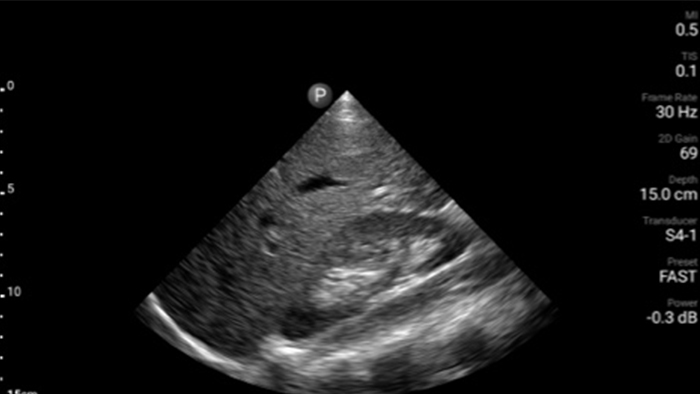

Ultrasonografia przy łóżku pacjenta

System Lumify do badań POCUS może być niezwykle cennym narzędziem do oceny stanu treści żołądka, które może obniżyć ryzyko jej aspiracji do płuc, a tym samym ryzyko powikłań po zastosowaniu znieczulenia.

• Rozszerzony zakres częstotliwości roboczej od 4 do 1 MHz • Obrazowanie 2D, kolorowy Doppler, tryb M-mode, zaawansowana technika XRES oraz wielowymiarowe obrazowanie harmoniczne • Obrazowanie w wysokiej rozdzielczości do badań jamy brzusznej i serca: optymalizacja predefiniowanych ustawień badań serca, położniczo-ginekologicznych, płuc, jamy brzusznej oraz FAST.